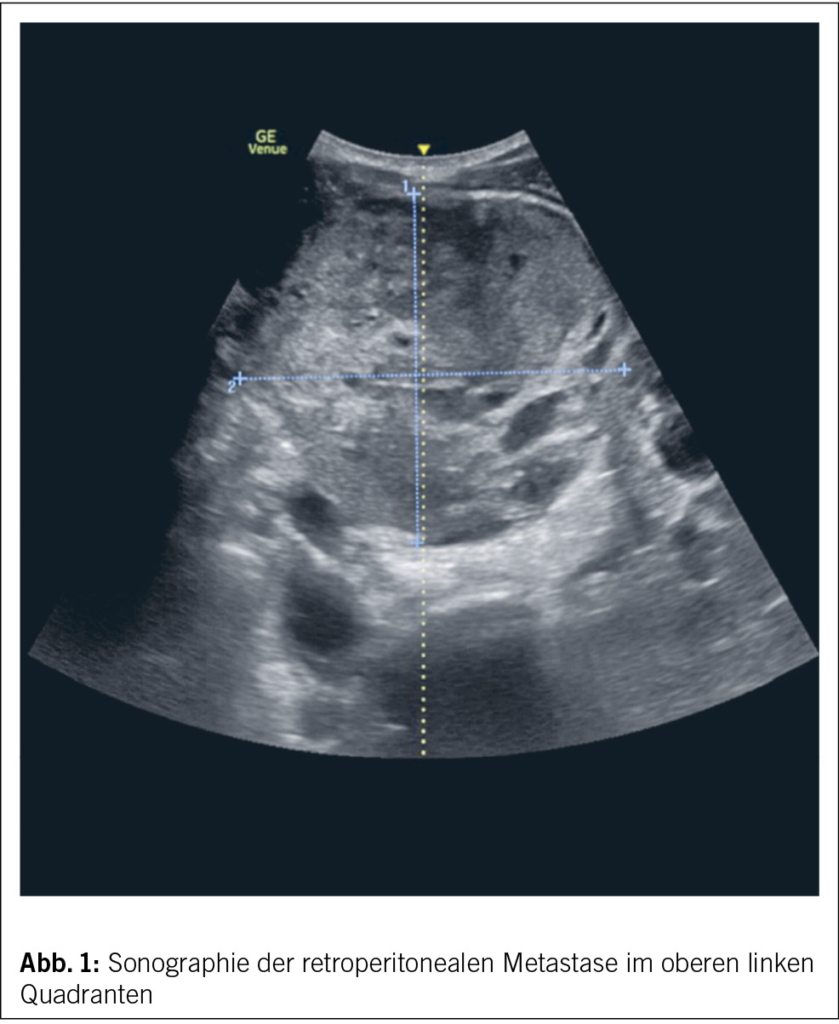

Ein 24-jähriger Patient stellte sich im Dezember letzten Jahres in der Notfallpraxis unseres Kantonsspitals vor. Er klagte zum Zeitpunkt über eine seit drei Wochen bestehende, palpable Masse im linken oberen Hemiabdomen. Auf Nachfrage verneinte er weitere Beschwerden. Der Patient fühlte sich zum Zeitpunkt der Konsultation unverändert fit und leistungsfähig. Die persönliche Krankengeschichte des Patienten war bis zu diesem Zeitpunkt blande. In der klinischen Untersuchung zeigte sich eine derbe, nicht verschiebliche Masse von rund 10 x 10 cm Ausdehnung. Auf Druck zeigte sich die Masse indolent. Die darüberliegende Haut zeigte keine Auffälligkeiten. Differenzialdiagnostisch gingen wir bei fehlenden Infektzeichen nicht von einer infektiologischen Ursache, insbesondere einem Abszess, aus. Aufgrund der Indolenz und des raschen Wachstums musste an eine maligne Erkrankung gedacht werden. Wir gingen am ehesten von einer Metastase aus. Zur Diskussion standen insbesondere lymphatische Malignome oder Hodenkarzinome. In der durchgeführten Bedside-Sonographie zeigte sich ein 9 x 10 cm grosser, inhomogener Tumor retroperitoneal (Abb. 1).

In der ergänzend durchgeführten Computertomographie des Thorax und Abdomens wurde der sonographisch und laboranalytische Verdacht im Sinne eines Hodentumors mit grosser retroperitonealer Lymphknotenmetastase bestätigt und der Patient den Kollegen der Urologie und Onkologie zugewiesen.

Die Überlebensrate ist im Vergleich zu anderen Krebserkrankungen sehr gut. Die 10-Jahres-Überlebensrate beträgt bis 95 % (2). Bei metastasierten Tumoren in der Poor-Prognosis-Group liegt die 5-Jahres-Überlebenswahrscheinlichkeit bei 48–64 % (10, 11). Zusammenfassend ist es wichtig, bei entsprechendem klinischen Verdacht eine umfassende Untersuchung und Organisation der Behandlung einzuleiten. Eine interdisziplinäre Zusammenarbeit mit den Kollegen der Onkologie und Urologie ist dabei von zentraler Bedeutung. Der Fall repräsentiert deutlich auch den Stellenwert der Sonographie für die Notfall- wie auch Hausarztmedizin.